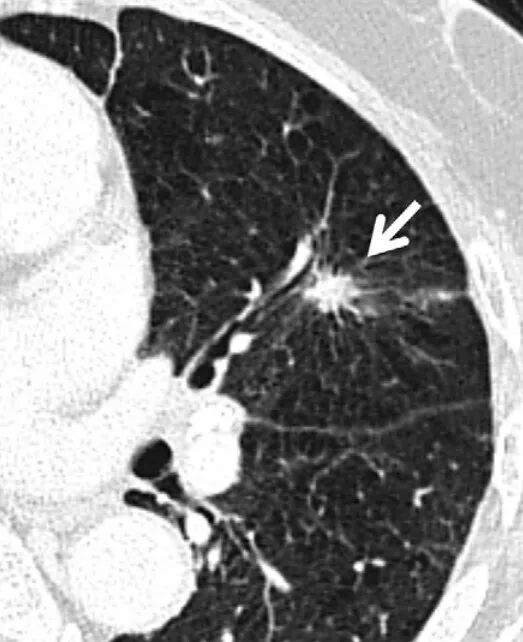

3.3肺结节形态

①持续性肺结节影像学表现为分叶、毛刺、胸膜改变(胸膜牵拉、胸膜皱缩、胸膜附着、胸膜凹陷)、空泡征和血管征(扭曲/扩张/僵硬)及囊腔型等征象者恶性概率高。

②影像学形态如毛刺、分叶、胸膜改变(胸膜牵拉、胸膜皱缩、胸膜附着、胸膜凹陷)、空泡征、血管征(扭曲/扩张/僵硬)及囊腔型等恶性征象者;